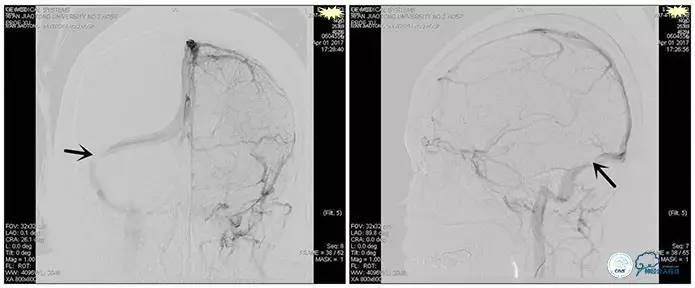

术后造影

术毕远近端压力差为:0